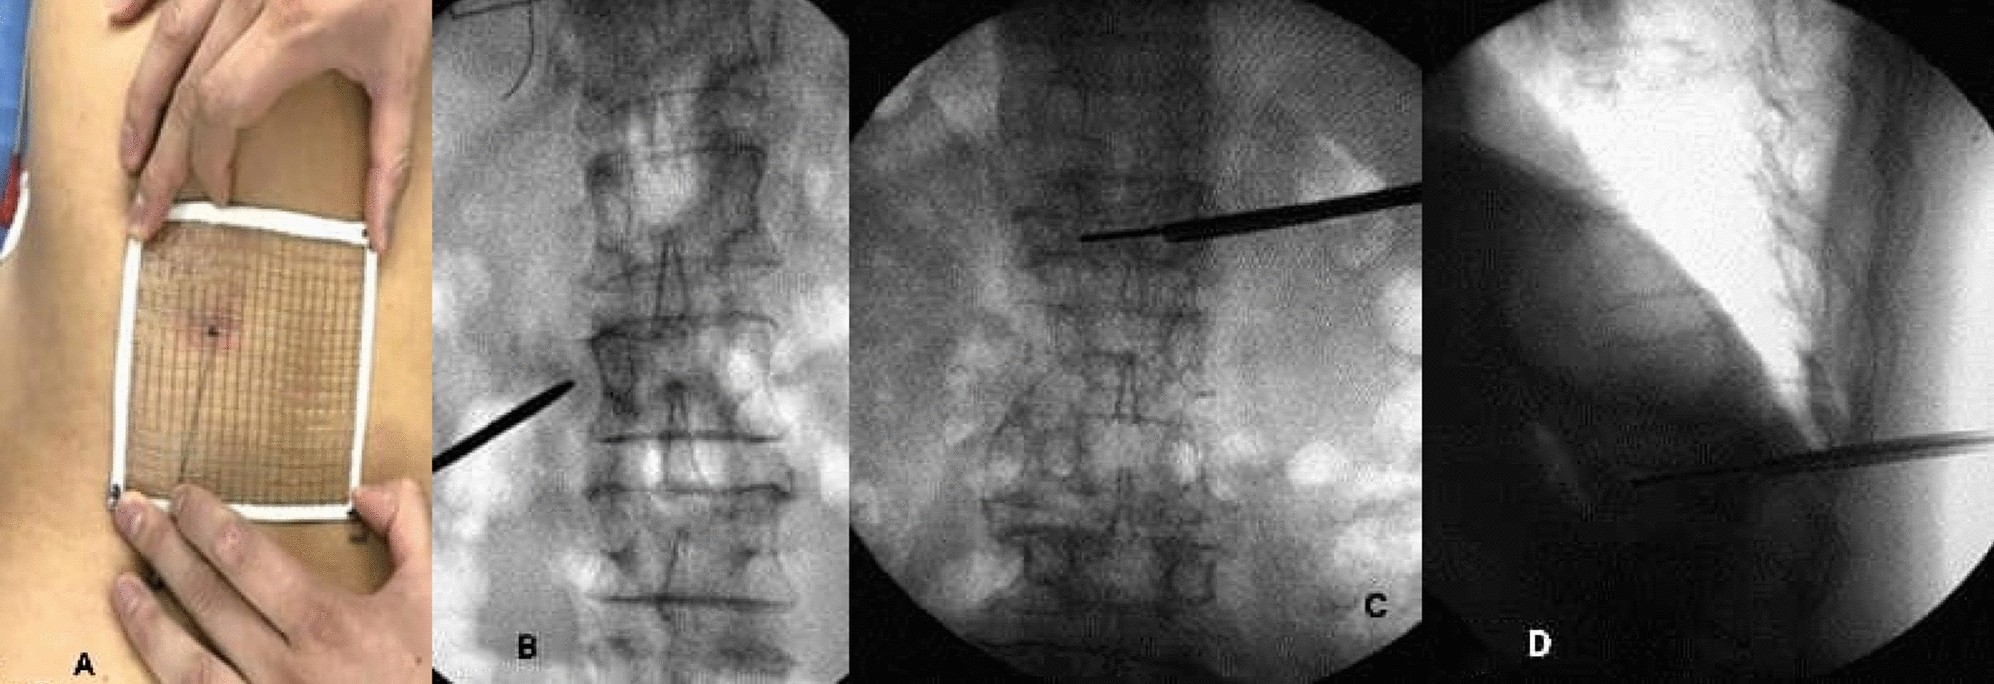

Figure 1

(A) Key puncture points of preoperative mesh optimization. (B) X-ray fluoroscopy showing the intersection of the midpoint of the line between the upper and lower endplates of the vertebral body and the tangent of the lateral edge of the pedicle of the vertebral body. (C) X-ray fluoroscopy to determine the target point in the vertebral body, where the tip of the guidewire reached the inner edge of the contralateral pedicle. (D) X-ray fluoroscopy showing the tip of the guidewire reaching the anterior edge of the vertebral body.